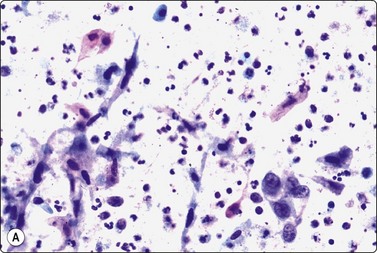

Epithelial atypia and squamous metaplasia are particularly prominent in necrotising sialometaplasia. This is a self-healing inflammatory condition of unknown etiology, possibly related to previous surgery, radiotherapy or infarction, which mainly affects minor salivary glands.98 Cellular smears of squamous metaplastic cells showing regenerative atypia and degenerative changes with necrotic material in the background can closely mimic well-differentiated squamous cell carcinoma (Fig. 4.27). Worrysome squamous epithelial cell atypia can be found in a wide spectrum of salivary gland lesions, causing diagnostic difficulties in FNB.99

image

Fig. 4.27 Necrotising sialometaplasia

(A) Seminecrotic material including degenerate squamous epithelial cells with pyknotic spindle nuclei resembling cells of cystic squamous carcinoma; (B) Metaplastic squamous epithelial cells showing mild reactive atypia (MGG, HP); (C) Corresponding tissue section (H&E, IP).